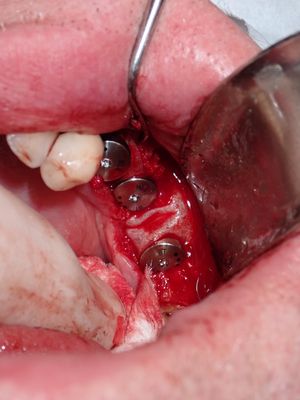

Bone loss noted, bone graft required, upon flapping, decided to place implants. Difficult case due to very strong macroglossic tongue, limited sulcular space. Short and wide implants placed, all socket/defects grafted with sticky bone from cortical allograft. membrane placed interimplant and fibrin membrane also used